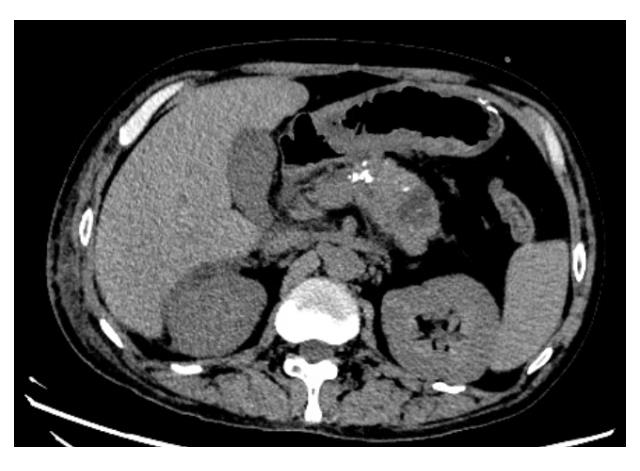

Jinping ZHANG,Lingling TONG,Lu GAO,Hongjing CHENG,Minjia SHENG.

Parasitic leiomyoma of abdominal wall complicated with disseminated peritoneal leiomyomatosis : A case report and literature review

[J]. Journal of Jilin University(Medicine Edition), 2024, 50(5): 1432-1437.